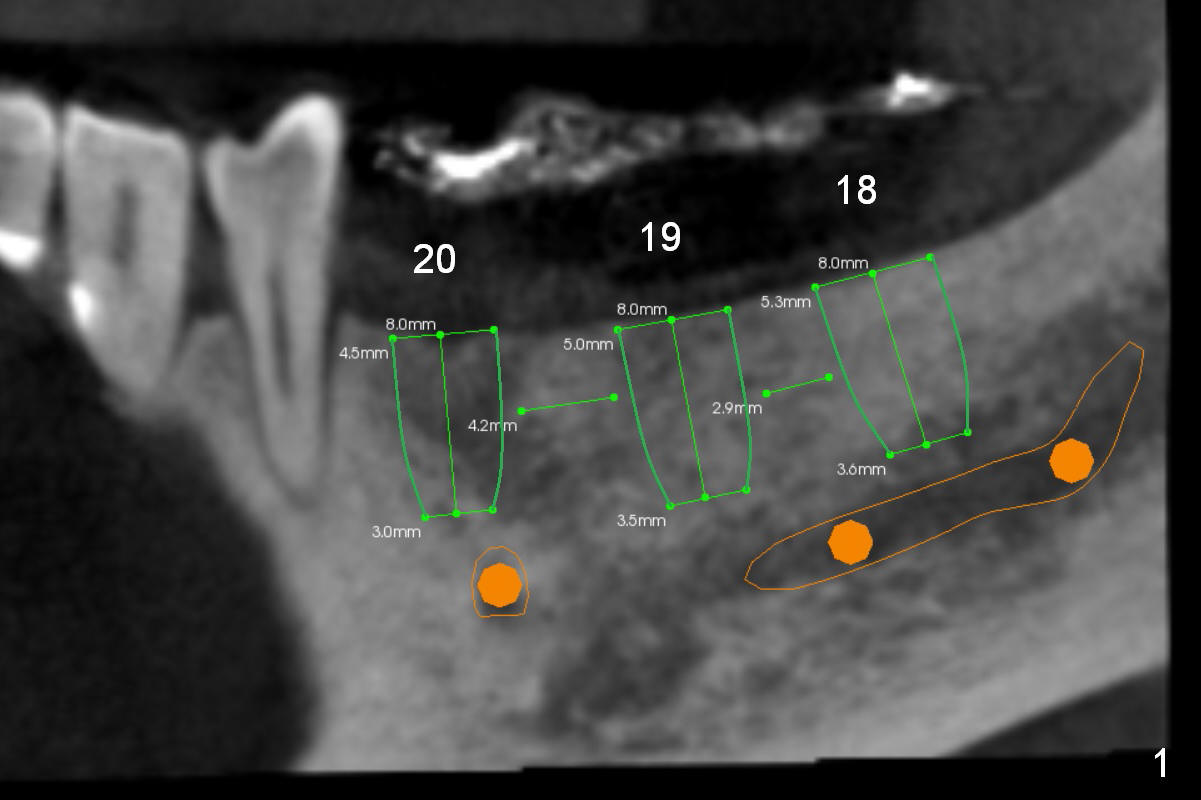

A 52-year-old man requests restoring 3 lower left posterior teeth (Fig.1-4). It appears that height is the biggest challenge: 6 or 8 mm implants seem to be proper choice.